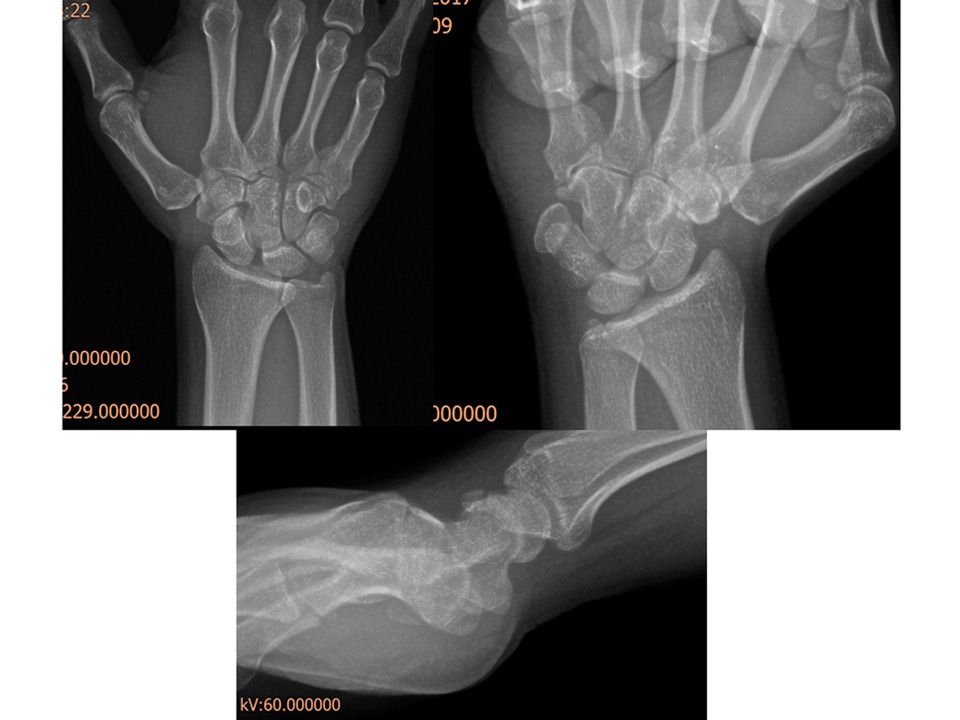

35 y, male, interior decorator, right hand dominancy Fall on an outstreched hand 1,5 months ago Wrist flexion 30° extension 45° Pain at anatomical snuff box